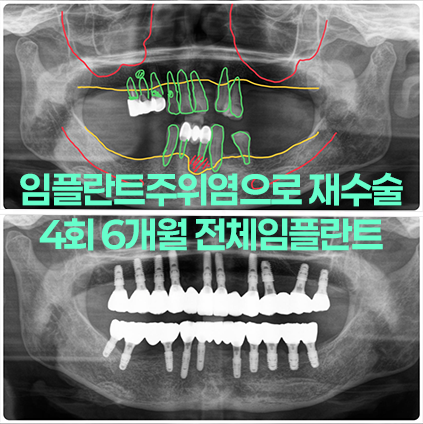

임플란트주위염으로 실패한 임플란트 제거와 많이 흔들리는 치아들 발치 후 전체임플란트